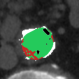

At this point, the dataset is ready for the processing in the portal ImageLab. The latter, takes as input the basal ROI and its corresponding CM one, together with their respective binary masks. These, are used by the algorithm to create the image (see Fig. 2), and consequently to detect the vessel. As depicted in Fig. 4, in output the extracted image is provided, along with a colored map where green highlights pixels correctly classified by the algorithm, red indicates misclassified ones, and white indicates the areas the algorithm should have identified but did not. Adjacent to this, similarity indices described before are presented, computed by considering the CM image as the target, which is provided as input for this purpose. We have processed in the portal each slice of our dataset.

In this version of the algorithm (updated compared to the one described in [30]), the calcium plaques are excluded from the patent lumen of the vessel and therefore visible in the processed image (in black), as we can observe also from Tables 3 and 4. The advantage of removing these structures during the extraction process leads to a more accurate and faithful evaluation of the indices. This observation is illustrated in Figure 6, where we present a comparison of results for a single slice obtained using the previous algorithm version, which does not remove calcium plaques from both the basal and the CM images, and the new algorithm version. The performance improvement is evident, particularly in the DCI index, where a difference is observed: of white pixels are accurately classified with the old version, compared to with the new version. Finally we highlight how, in the new version of the algorithm, the removal of the calcium plaques from both the basal and the CM images produces a different extraction of the patent lumen of the vessel, which in addition to being compatible with the algorithm’s steps, also turns out to be more accurate.

![]() |